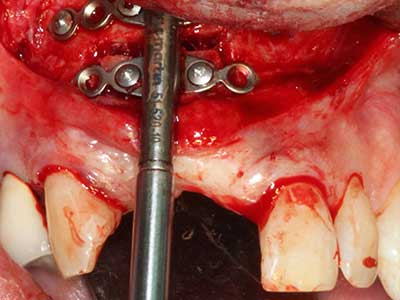

Fig. 18: preparazione di una copertura corticale con sega piezoelettrica per osso (Piezomed, W&H).

Fig. 19: sito chirurgico dopo neurolisi e rimozione dell'osteoma.

Fig. 20: la copertura ossea rimossa viene riadattata e fissata con una vite per osteosintesi (KLS Martin, Tuttlingen).